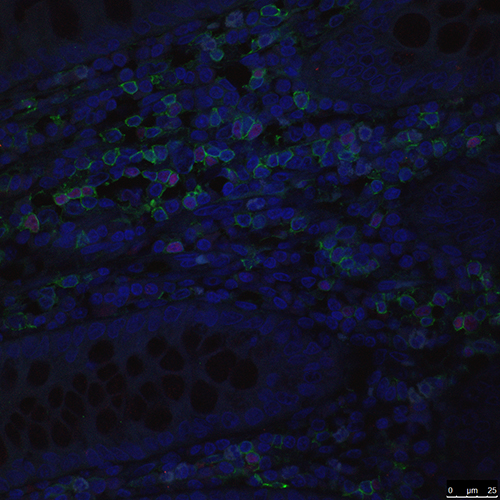

IBD CD4Foxp3-7 60X

Increased numbers of Foxp3+ regulatory T cells that accumulate in the colonic tissue of Crohn’s diseasepatients compared to colon sections taken from non-inflammatory bowel disease patients.